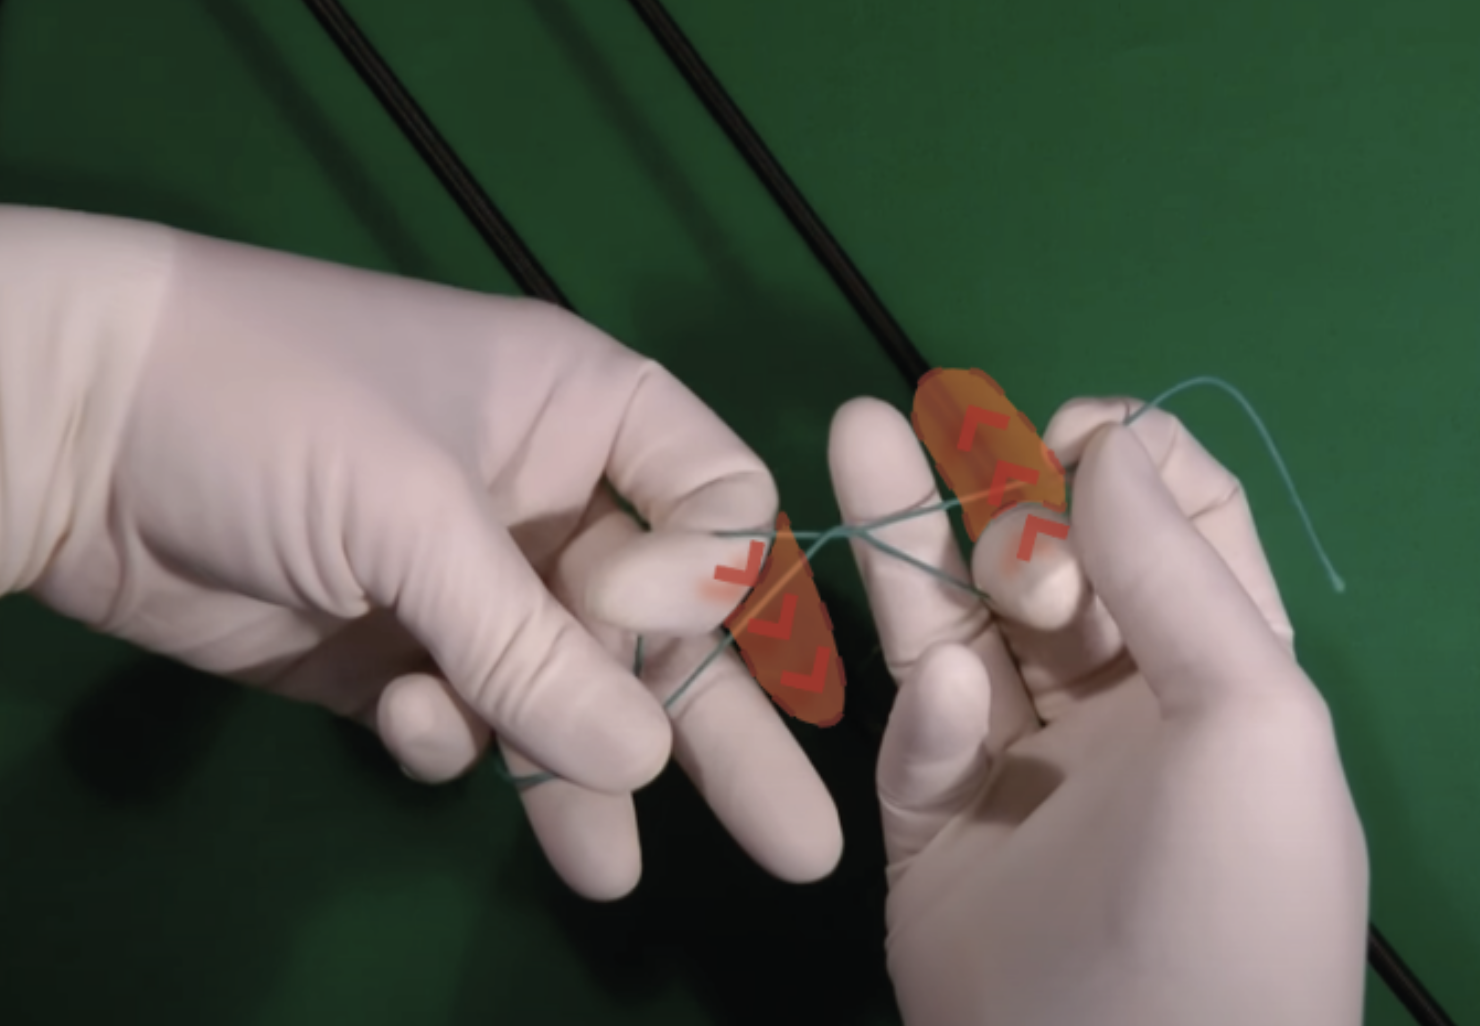

The objective of the project is to build an application that simulates surgical knot and suturing techniques. Based on new methods of machine learning for capturing hands and objects, the application should allow users to train fine manipulations of bodies and objects from a first person perspective in 4D space. While digital learning is usually based on observation and lacks interaction, the GreifbAR application will consist of virtual hands and other mixed reality elements that guide the user’s learning experience. The quality and accuracy of the user’s gestures and finger positions can be recorded and evaluated in real time.

The learning system is intended to be used for the teaching of surgical staff in the early career stages, where it seeks to improve the quality of education, reduce training costs and minimize risks and the use of animal experiments. The expansion to other surgical learning situations is planned.